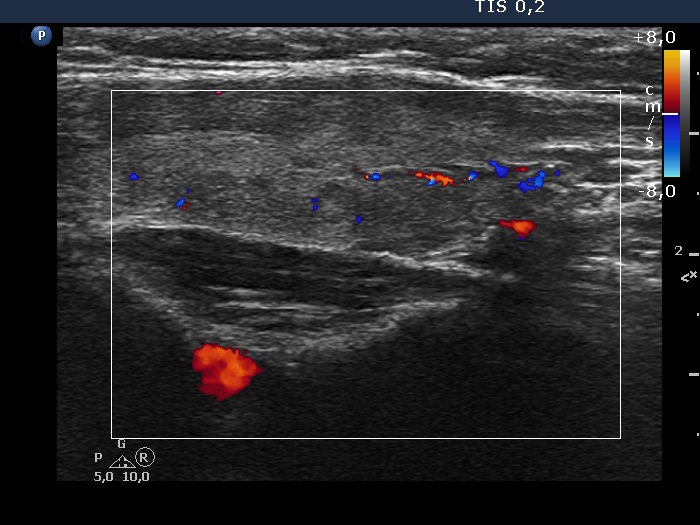

Left lobe, longitudinal scan, color Doppler mode. The vascularization is average.